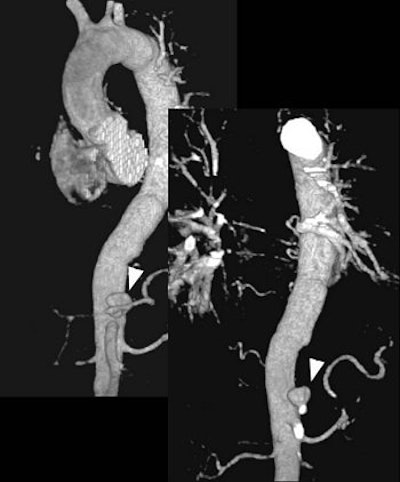

The initial entry site of Stanford B and its relationship with left subclavian artery (top images, both VR).

![]() |